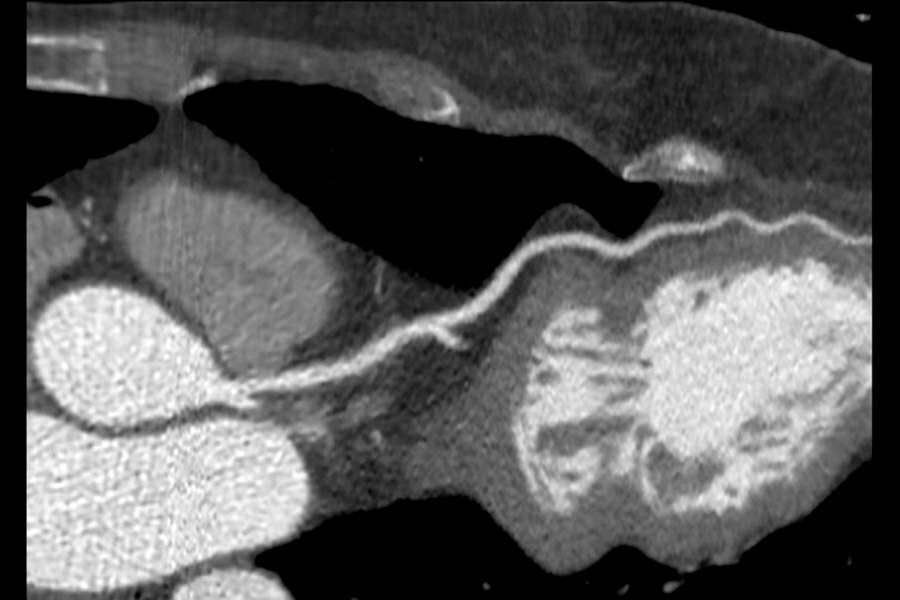

Visualization of the lumen on calcified RCA. BMI 28, HR 57